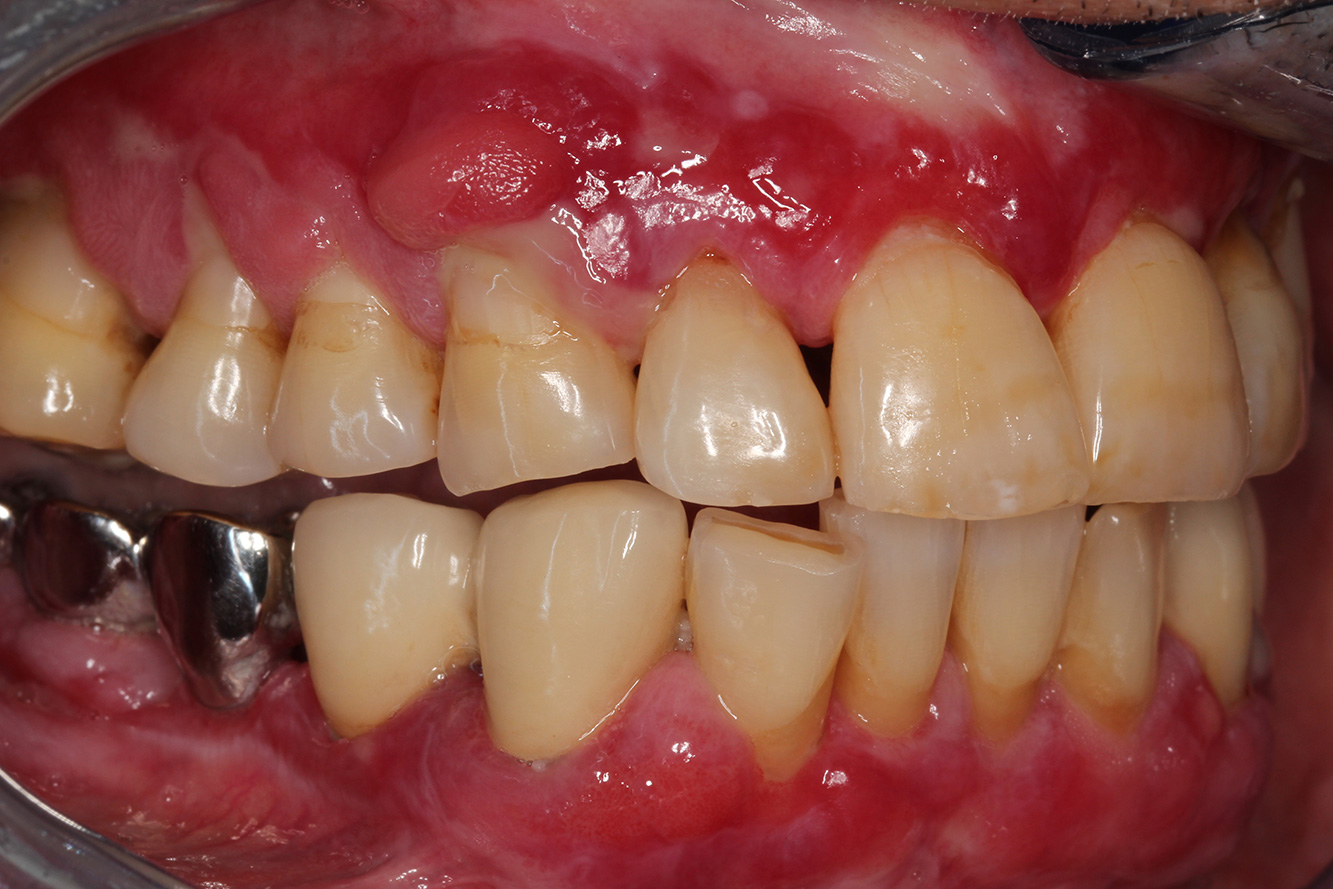

Se presenta un paciente de 71 años con trasplante de riñón e hipertensión (presión arterial alta). Debido a su historia médica, es necesario el tratamiento continuo con ciclosporina para suprimir el sistema inmunitario y amlopidina para bajar la presión arterial. Además, el paciente relata encías sensibles y sangrantes. Desde el punto de vista de la salud oral, hay dientes restaurados con ocho piezas faltantes, hiperplasia gingival pronunciada, periodontitis en fase II, de grado B con bolsas activas y una caries inicial en la pieza 22. En la evaluación del riesgo de caries se ha establecido un riesgo de caries medio (API 60). Para la sesión de profilaxis se hacen las siguientes recomendaciones.

Con base en la historia médica, se detecta un riesgo de complicaciones importante. Debido al trasplante de riñón, el paciente está inmunodeprimido (ciclosporina), también tiene el sistema inmunitario debilitado y necesita profilaxis para infecciones (recomendación: 2 g de amoxicilina como antibiótico 1 h antes de la sesión). Al mismo tiempo, el tratamiento continuo hace que el paciente tenga un mayor riesgo de enfermedad, dado que la hiperplasia gingival establecida está asociada a la medicación (20).

Se debe abordar la situación del paciente, especialmente cuando se trata de motivación y aprendizaje. La hiperplasia gingival dificulta la higiene oral en casa. La mayor susceptibilidad a las infecciones y el progreso y la nueva formación de hiperplasias (22) debe hablarse de igual a igual. Al mismo tiempo, deben explicarse las técnicas de higiene adecuadas según las necesidades individuales.

Para el paciente se recomienda un intervalo de control posterior más corto, de tres a cuatro meses. Esto se debe principalmente a la hiperplasia gingival asociada a la medicación, la situación de cuidado difícil asociada y el alto riesgo de progresión de la periodontitis.